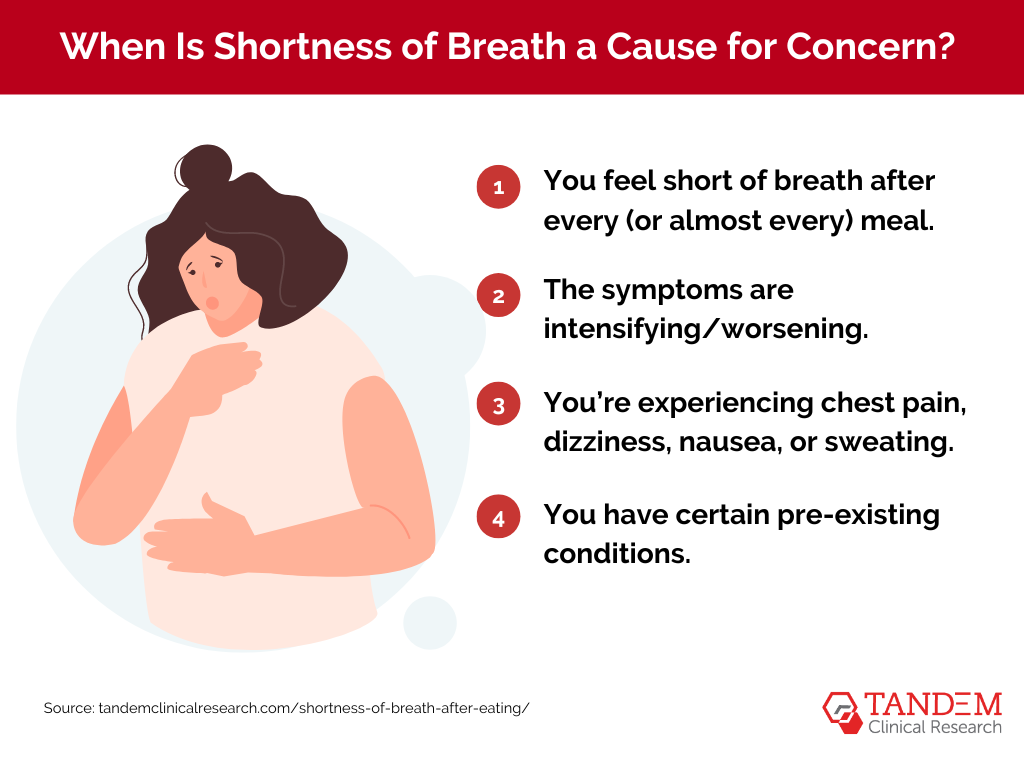

What Causes Shortness Of Breath After Eating Tandem Clinical Research

https://www.tandemclinicalresearch.com/wp-content/uploads/2024/02/shortness-of-breath-concerns.png